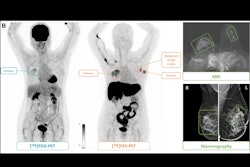

The study was led by Yun-Woo Chang, MD, from Soonchunhyang University Seoul Hospital in collaboration with breast and general radiologists from six South Korean academic hospitals. It included 24,543 women aged 40 and above who underwent routine biennial mammography as part of Korea's national breast cancer screening program between February 2021 and December 2022; it compared the performance of radiologist screening mammography interpretation with and without the use of Lunit's Insight MMG.

- AI-assisted radiologists detected 13.8% more screen-detected breast cancers than those relying solely on conventional interpretation methods.

- The cancer detection rate (CDR) increased from five per 1,000 to 5.7 with AI assistance.

- AI assistance led to a significant improvement in identifying small-sized tumors and node-negative cancers.